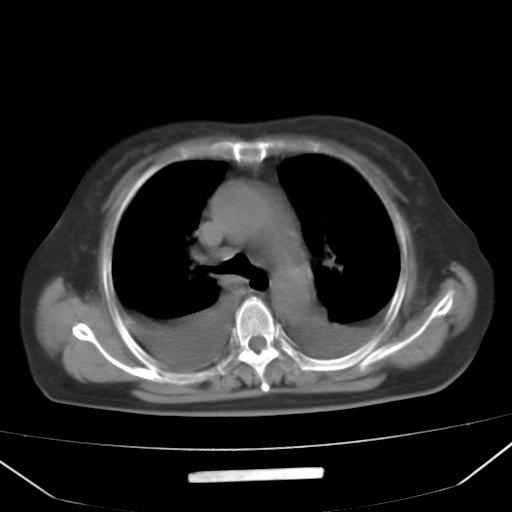

以下是引用liuyue在2008-4-19 22:25:00的发言:[br]先考虑:1.心衰伴肺水肿、双侧胸腔积液、叶间积液、双下肺不完全性肺不张; [br] 2.冠状动脉粥样硬化。

以下是引用lijuanln在2008-4-19 23:05:00的发言:[br]两侧胸腔积液,肺水肿[br]心包积液[br]提示心衰

以下是引用jiangjing在2008-4-20 10:43:00的发言:[br]结合病史支持 冠心病[冠状动脉钙化],心功能不全,肺淤血、肺水肿,双侧胸腔与斜裂积液